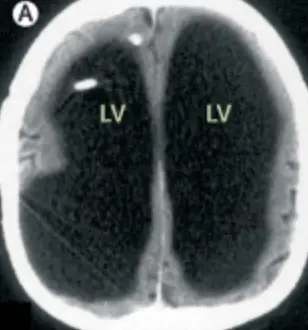

So, when doctors scanned his brain to access the cause of his unexplained leg weakness, they were surprised to find that he had an enormous fluid-filled chamber.

However, this man's brain fluid built up, which left him with a massive deposit of liquid and very little brain matter.

The doctors learned that the man had a condition called Hydrocephalus, a build-up of fluid in the brain; he actually had a shunt placed inside his head at just six years old to drain the fluid, but it was removed when he turned 14.

Speaking about the case, Feuillet confirmed that the fluid buildup had led to a significant reduction in brain matter: "It is hard for me [to say] exactly the percentage of reduction of the brain, since we did not use software to measure its volume. But visually, it is more than a 50 to 75 percent reduction.

"The whole brain was reduced – frontal, parietal, temporal, and occipital lobes – on both left and right sides. These regions control motion, sensibility, language, vision, audition, and emotional and cognitive functions," Feuillet went on to tell New Scientist.